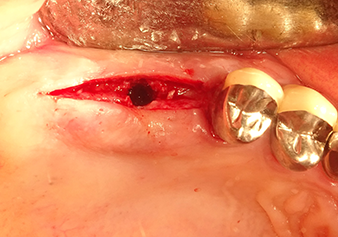

Implant bed preparation and augmentation

Following an intermediate check (Fig. 4) a further preparation step was performed (Fig. 5). Afterwards, the hydraulic Z35P instrument was used to lift the membrane to the desired position (Fig. 6 and 7). This was followed by further piezosurgical preparation of the implant bed, concluded with a rotary bur and shoulder milling cutter up to the implant diameter of 4.8 mm. Before the implant was inserted, the augmentation material (particle size approx. 0.8-1.6 mm) was introduced underneath the Schneiderian membrane (Fig. 8).

The Schneiderian membrane is stretched 1.5-2 mm above the bony access

Fig.4: Intermediate check: The bone height above the maxillary sinus floor is approx. 4 mm palatal and buccal; the Schneiderian membrane is stretched 1.5-2 mm above the bony access.